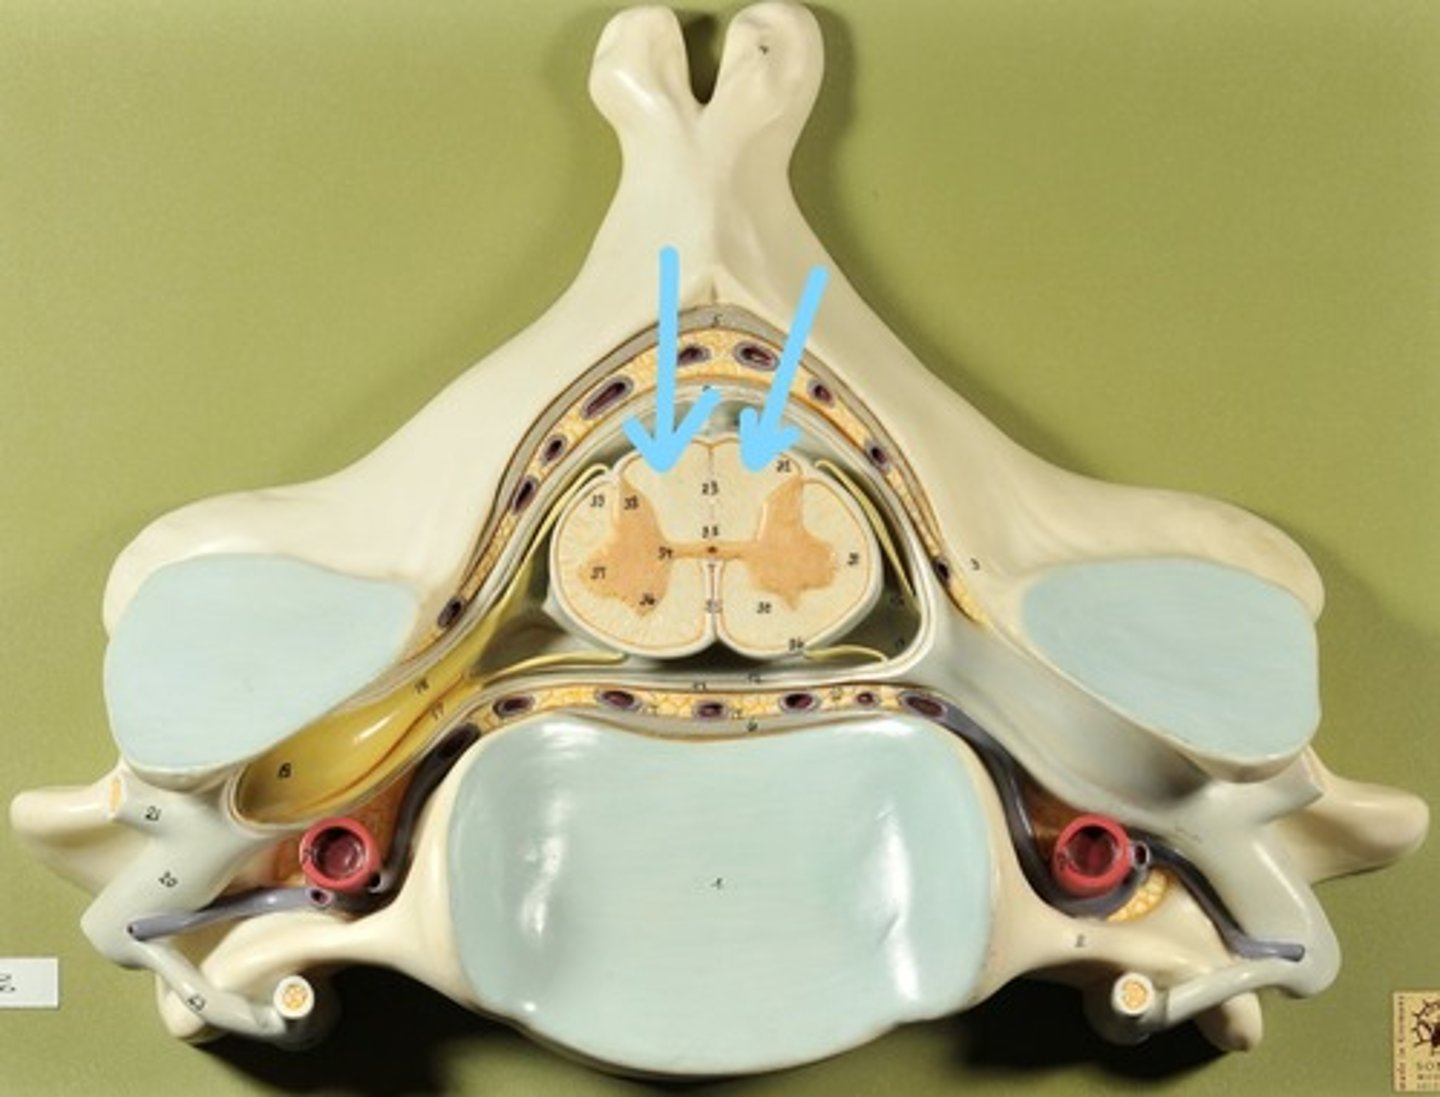

Identify all structures of spinal cord

White Matter of spinal cord

gray matter of spinal cord

Ventral Horns (gray matter)

Lateral Horns (gray matter)

Dorsal horns (gray matter)

Anterior Columns (white matter)

Lateral Columns (white matter)

Posterior Column (white matter)

central canal of spinal cord

Identify all structures

Pia Mater

Subarachnoid Space

Arachnoid mater

Subdural Space (brown line)

Dura mater

Epidural Space

Dorsal Root Ganglion

Dorsal Root

Ventral Root

Spinal Nerve